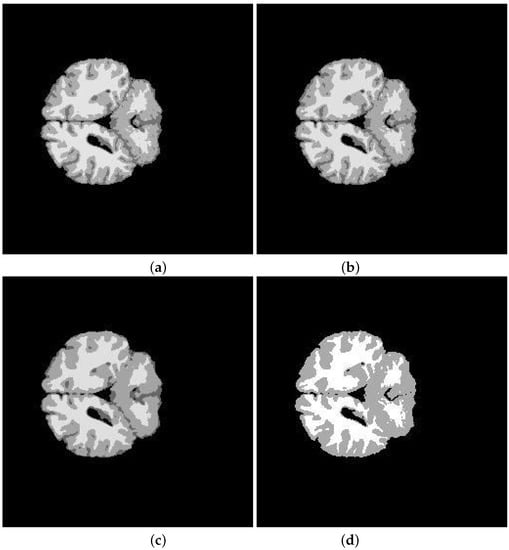

5. Application and Results